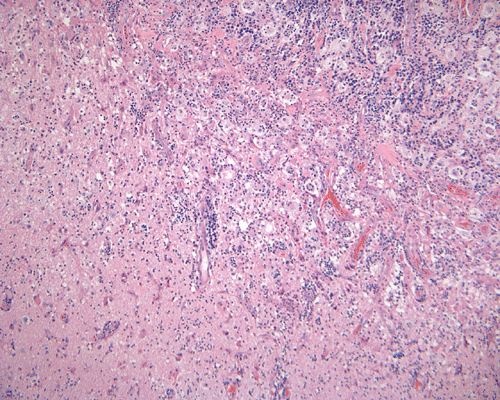

The specimen is in the form of a plaque-like, firm lesion adhered to a layer of brain parenchyma on one side (Panel A) The lesion infiltrate into the underlying brain parenchyma which leads to the formation of an irregular interphase. There is also perivascular accumulation of lymphocytes around blood vessels (Panel B  and C). On low-mangification, the lesion appears to be a mixture of lymphocytes and large cells with foamy histiocytes. The salient feature of the lesion is that of a mixture of mature lymphocytes with large to giant histiocytes (Panel D). The histopathologic picture is rather homogeneous in different parts of the lesion. On high-magnification, the large to giant histiocytes has enlarged nuclei and many of them contain engulfed lymphocytes or polymorphonuclear leukocytes (emperipolesis ) (arrows in Panel E an F).

Histiologically, the features of cranial RDD are similar to those occurring in the lymphnodes.  Lesions are composed of sheets or syncytia of large, pale histiocytic cells with abundant granular eosinophilic cytoplasm and ill-defined or feathery cytoplasmic borders in a lymphocytic, chronic inflammatory cell background. Extranodal sites commonly exhibit a degree fibrosis and this can obscure the visibility of the histiocytic proliferation. Nuclei of the large histiocytes vary in size and may be large, round and vesicular with smooth nuclear contours 2. A mild degree of cytological atypia is commonly seen.  Most nuclei contain a single small nucleolus, but others possess multiple nucleoli or a single prominent nucleolus. Mitotic figures are usually difficult to detect or are absent altogether. The prominent background of chronic inflammation is largely comprised of a mature plasmacytic infiltrate with interspersed lymphoid follicles 2.  Emperipolesis is consistently found in nodal disease and often is less evident at extranodal sites.  Its recognition is key to correct diagnosis.